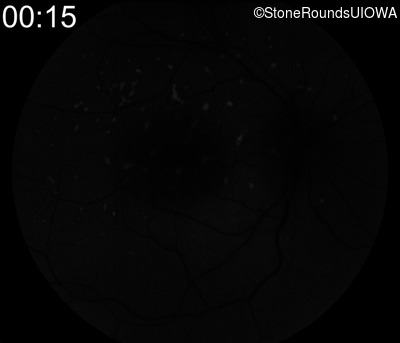

Fluorescein Angiography - Left - 20/40 +1 sc

Exemplar